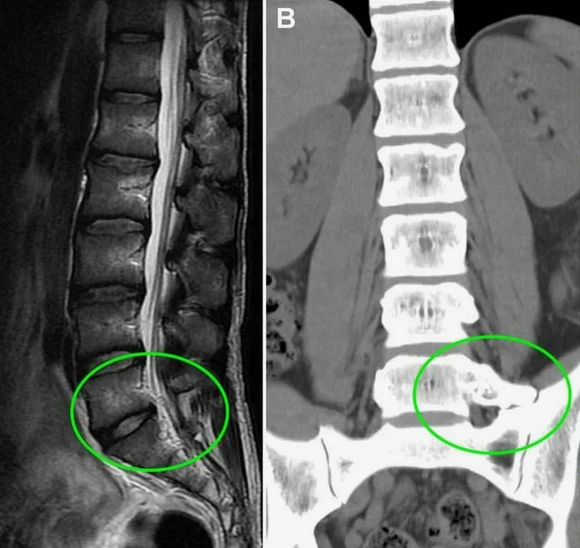

Магнитно-резонансная томография (МРТ):один из самых эффективных методов диагностики заболеваний